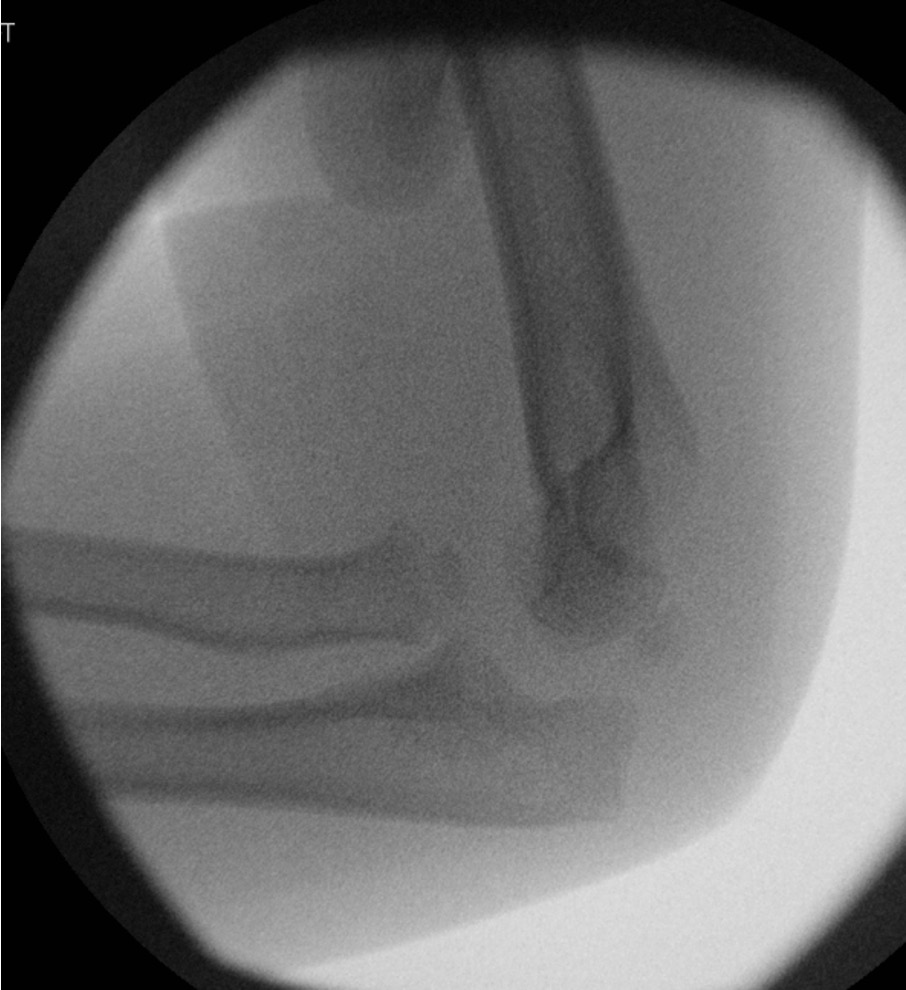

Retrograde flexible nail

Technique

Entry point through radial styloid

- closed reduction +/- percutaneous K wire reduction

- engage tip into radial neck

- Metaizeau technique - rotate nail to reduce radial fracture